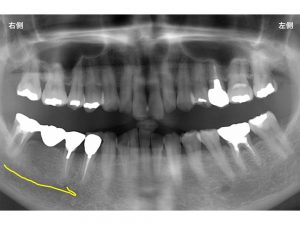

その一つとなるのが神経の位置です。

下顎の顎には、下顎神経という太い神経が通っています。

以下の黄色線です。

もちろん神経に触れてはいけません。

インプラントと神経の距離は2ミリ以上ないといけません。